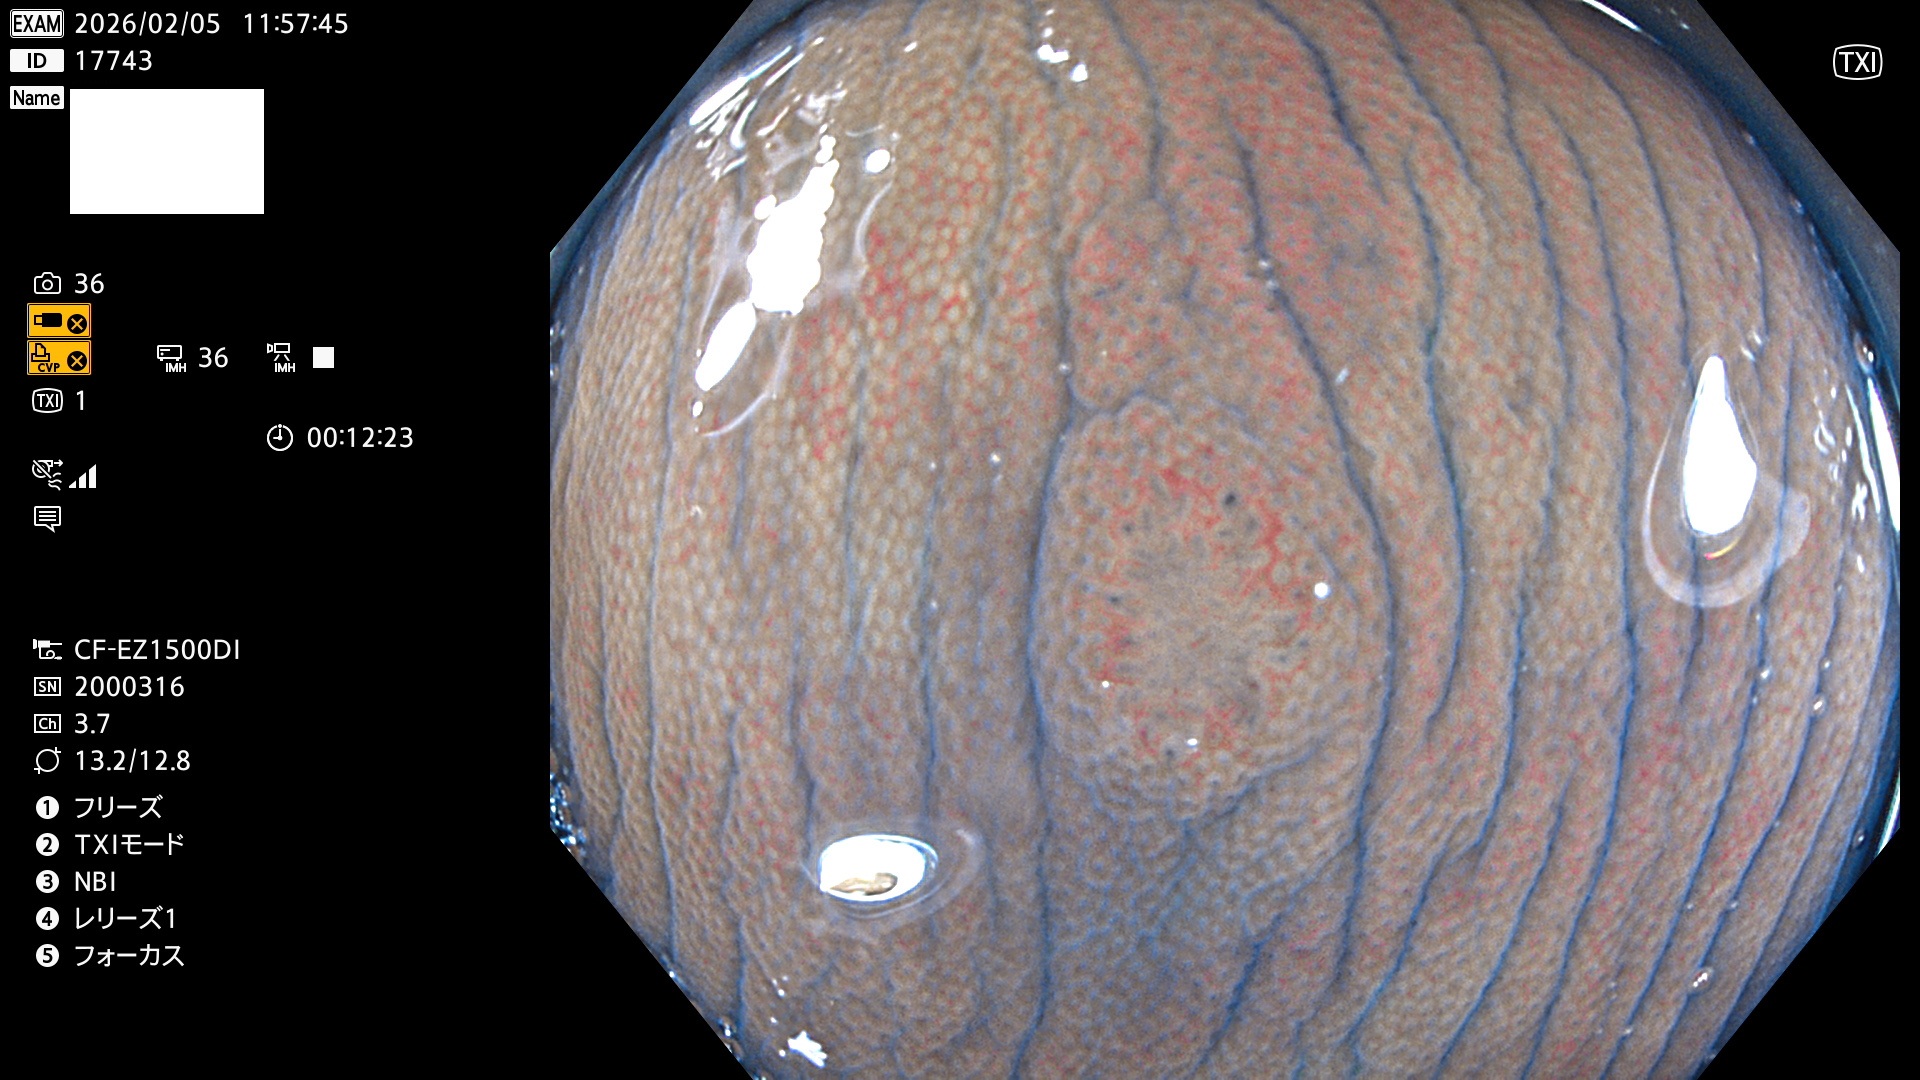

完全に平坦な物をUb、陥凹している物をUcと呼びます。Ubは認識が困難で、Ucはびらん(炎症)と紛らわしいために見落とされやすく、「内視鏡後・大腸癌」の原因になります。

2026年2月5日〜2月8日の4日間(40件)で9個 (Uc_ADR=9個/40人=23%)